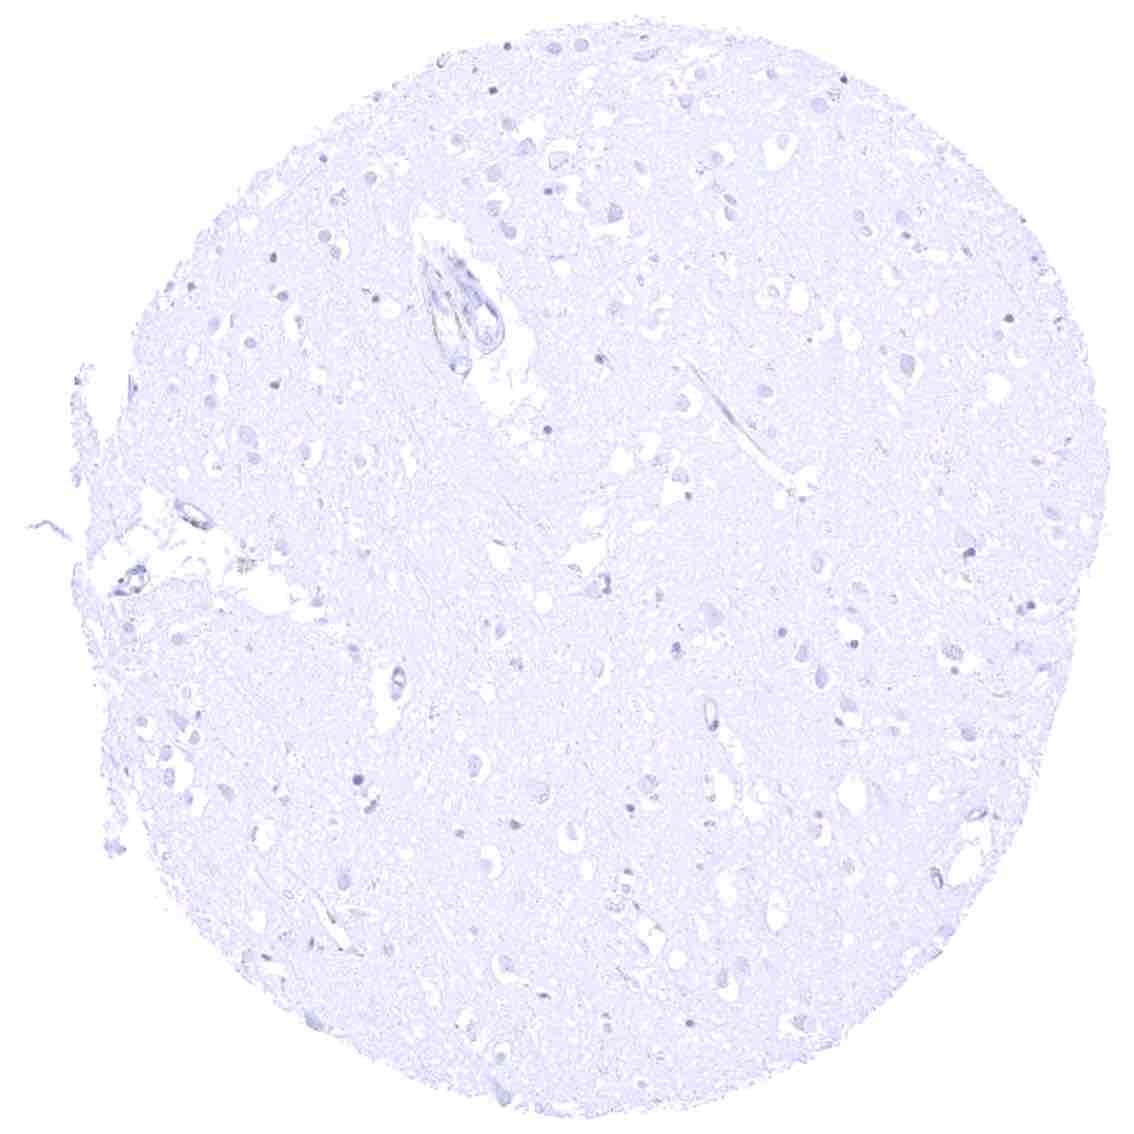

Cerebrum (grey matter)

Cerebrum (white matter)